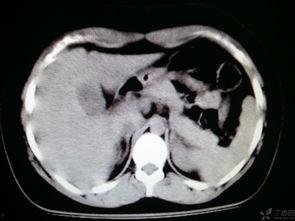

异位妊娠是指受精卵在子宫腔外着床,如输卵管、卵巢等。异位妊娠会导致输卵管破裂,引起剧烈的下腹部疼痛。如果不及时治疗,还可能危及生命。

5. 结石

肾结石和输尿管结石是常见的泌尿系统疾病,会导致下腹部疼痛。结石在移动过程中会刺激输尿管,引起剧烈的疼痛。